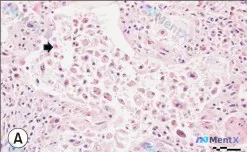

今天整理了一个很有警示意义的病理读片病例,整个分析过程差点被第一印象带偏,最终靠两个核心特征锁定了方向。 先看病例的核心影像与检查: - 图A(H&E,400X):显示大细胞嵌于密集淋巴样间质中,初看很像「淋巴上皮瘤样」形态;仔细观察可见Emperipolesis(胞内吞噬现象)——大细胞胞浆内有完...